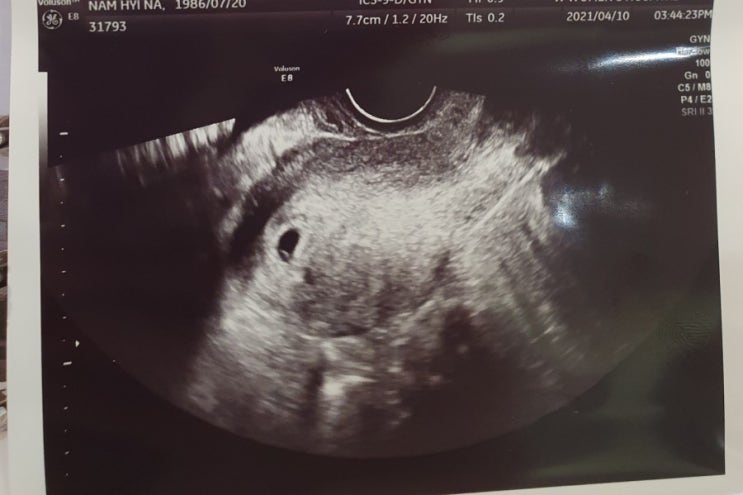

임신10주차 증상 새벽 소변 줄어듬 12주차까지 비슷함 인천w여성병원 1차기형아검사 결과

즐거운 집순이의 임신일기:) 이제 임신12주차이다. 그동안 10주부터 겪었던 일들을 기록해보려한다. 10주차...